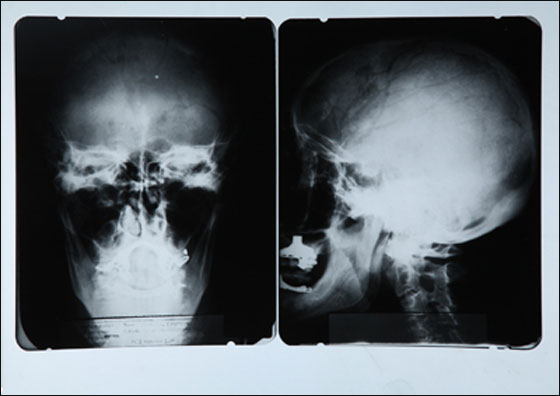

وتخلل المزاد بيع صورة أشعة لدماغ العالم ألبرت أينشتاين مقابل 38750 دولارا، وعلب أدوية فارغة تعود للنجمة مارلين مونرو مقابل 18750 دولارا، وقميص لملك الروك الراحل ألفيس بريسلي بـ90 ألف دولار.

صورة اشعة لدماغ البرت اينشتاين

البرت اينشتاين